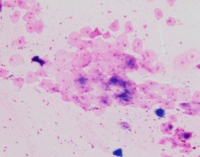

Medical Image Analysis: geckler3 could be used by healthcare professionals, researchers, and medical students to quickly and accurately identify White Blood Cells (WBC) and Erythrocyte-Hemoglobin Concentration (EHC) in clinical images, improving diagnosis and understanding of various blood-related conditions and diseases.

Blood Disorder Diagnosis Support: Implement geckler3 in diagnostic tools to assist doctors in identifying blood disorders, such as anemia or leukemia, by accurately analyzing WBC and EHC levels in blood images, helping with faster and precise diagnosis and treatment.

Biomedical Research: Utilize geckler3 in research laboratories for various biomedical and biotechnological studies to analyze large datasets of blood images, streamlining the process of data collection and analysis by automatically detecting WBC and EHC patterns.

Training and Educational Tool: Integrate geckler3 into educational platforms or applications to help medical and laboratory professionals, as well as medical students, learn and practice the identification of WBC and EHC in blood images, enhancing their skills and knowledge.

Remote Diagnosis Assistance: Employ geckler3 in telemedicine applications, allowing healthcare professionals to remotely access and analyze blood images for the presence of WBC and EHC, aiding in the diagnosis and management of blood-related conditions in areas with limited medical facilities.